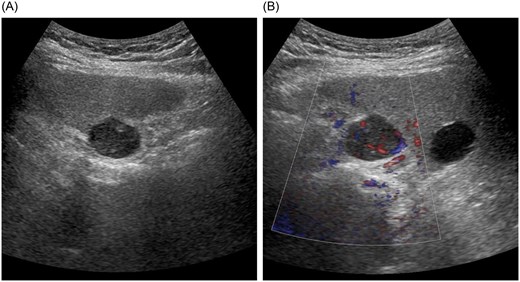

Abdominal ultrasonography demonstrated a well-defined, smooth-surfaced hypoechoic mass measuring ~23 × 19 mm protruding from segment 8 beneath the hepatic dome (Fig. 1A). The lesion contained an anechoic area and a solid component with pulsatile flow (Fig. 1B).

Abdominal ultrasonography findings. (A) A well-defined, smooth-surfaced hypoechoic mass measuring ~23 × 19 mm protruding beneath the hepatic dome in segment 8. (B) The lesion contains an anechoic area and a solid component with pulsatile flow.